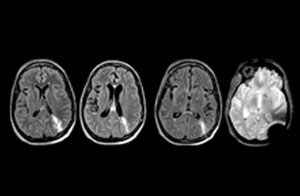

Cervical spine routine exam

This patient presented with headache that was worse with neck flexion and we see a Chiari 1 malformation with low-lying cerebellar tonsils as well as some degenerative cervical thrombolytic change.